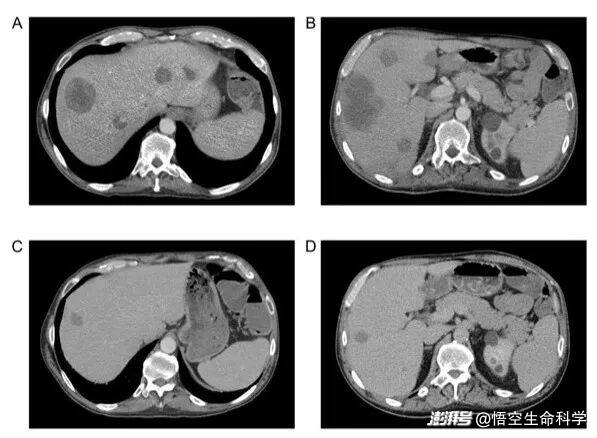

▲采用 RECIST v1.1 进行 CT 扫描,结果显示,接受 SNK01 和 pembrolizumab 联合治疗的放射性软骨肉瘤患者的肝脏结节大小显著减少。